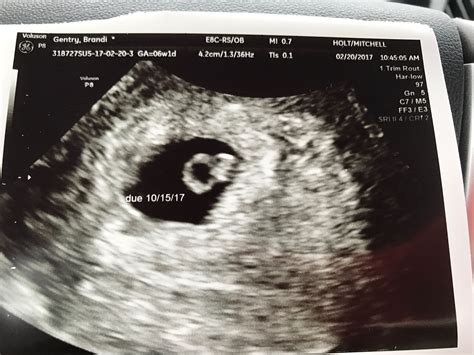

• Gestational Sac: The presence of a gestational sac confirms the pregnancy. It appears as a small, fluid-filled structure within the uterus.

• Yolk Sac: By week 6, a yolk sac may be visible. This structure provides early nutrition to the embryo and is a positive sign of a healthy pregnancy.

• Fetal Pole: The fetal pole is the earliest visible structure of the embryo. It appears as a small, curved line within the gestational sac.

• Fetal Heartbeat: A fetal heartbeat may be detectable by week 6, although it is more commonly seen by week 7. The heartbeat appears as a flickering motion on the ultrasound screen.

• normal 6 week ultrasound pictures